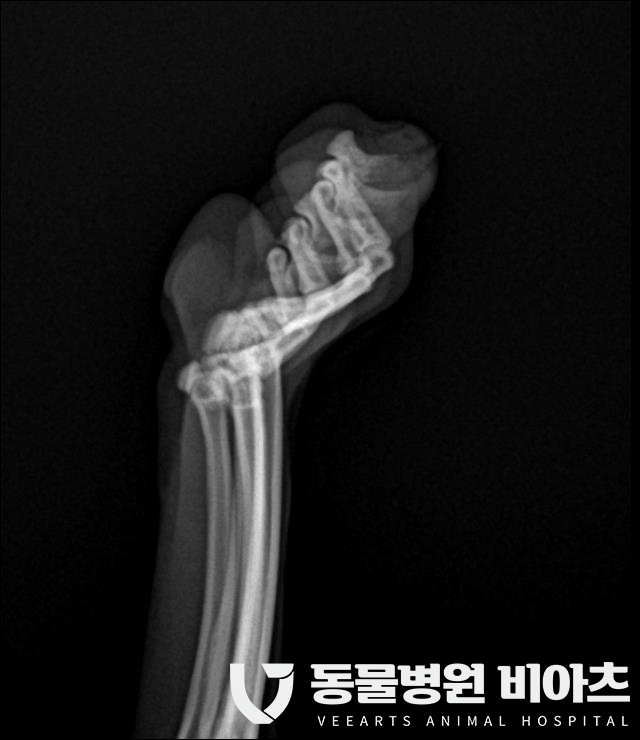

엑스레이 촬영

흉부 엑스레이와 발톱 부위의 엑스레이 촬영을 합니다.

마취 전 검사와 병변 부위의 검사입니다.

치료 (호흡 마취, 부분 골절된 발톱/ 육아종 제거)

골절된 발톱 부위에

염증이 많습니다.

염증이 생겨서 벌어진 틈으로 육아종이 증식하였습니다.

또한 출혈도 발생하고 있습니다.